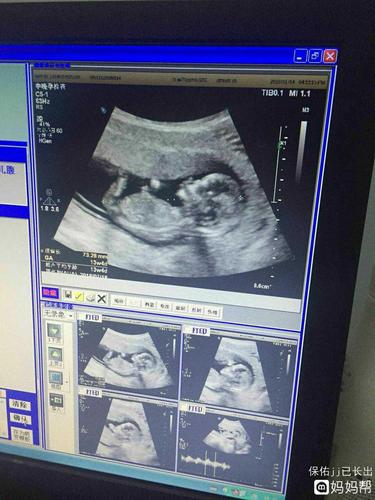

nt宝宝影像,会看男女的宝妈帮看看,谢谢!

宝宝十二周nt 彩超

nt过啦,给你们欣赏一下照片吧!能看出男

nt单可看男女准确率90nt可以看男女吗